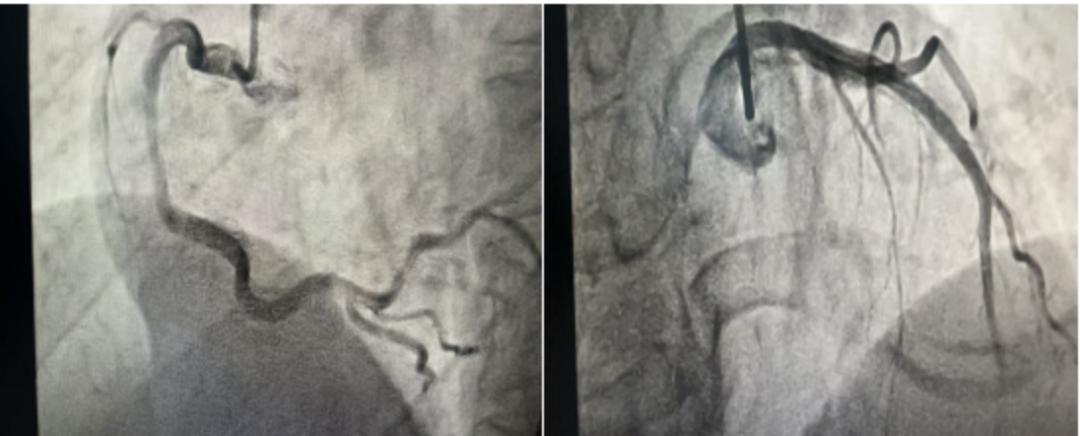

心血管内科主治医师袁梦婷会诊时,发现心电图提示心肌缺血改变。“老人的心脏情况是手术的关键,必须先做详细评估。” 袁医生建议进行冠状动脉造影,结果显示前降支中段中度狭窄。